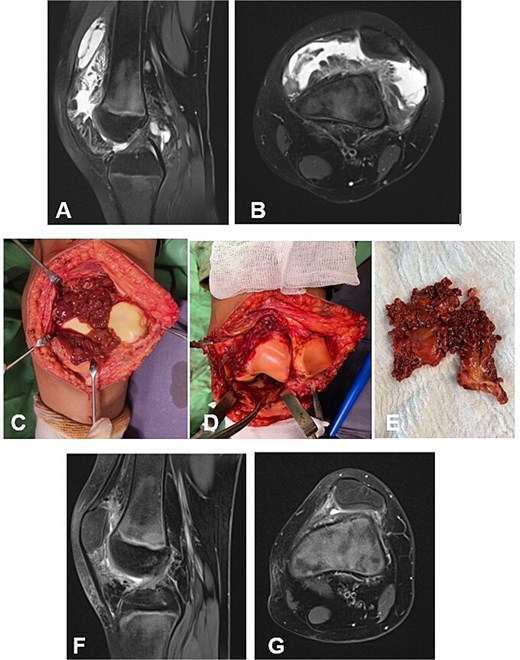

Case 1. (A and B) Preoperative T1 sagittal and axial MRI sequences with PD FS. (C and F) Macroscopic appearance of the pathological synovium before and after its excision. (D and E) The knee joint following synovectomy, demonstrating intact menisci and cruciate ligaments. Chondral lesions correspond to Outerbridge grade IV. (G and H) Postoperative 24 m. Sag and Ax MRI PD FS. No evidence of recurrence of the resected neoplasm was detected. Residual TGCT involvement persists within the lateral posterior femoral recesses. PD FS, proton density weighting with fat suppression; TSE, turbo spin echo.

A 4-year-and-5-month-old child presented with a history of chronic synovitis of the right knee joint persisting for more than 2 years. Progressive limitation of motion was observed—a 15° flexion contracture, and maximum flexion limited to 75°. Magnetic resonance imaging (MRI) was concordant with the intraoperative findings, demonstrating diffuse involvement of both anterior and posterior recesses of the knee joint (Fig. 2A–C). A subtotal anterolateral synovectomy was performed. Intraoperatively, chondral defects corresponding to Outerbridge grade IV were identified (Fig. 2C–E). At 2-year follow-up, a substantial improvement in the range of motion was achieved (Table 1). Follow-up MRI demonstrated no evidence of local recurrence in the previously resected area of the neoplasm (Fig. 2G–H). A secondary synovectomy is planned to address residual synovial involvement within the posterior lateral femoral recess.